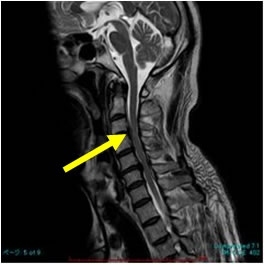

脊髄・脊椎疾患 | 名古屋大学大学院医学系研究科 脳神経外科学, 頚椎脊柱管狭窄症の症例と症状について|白石脊椎クリニック,

頚椎脊柱管狭窄症の症例と症状について|白石脊椎クリニック, 脊椎脊髄センター | 総合東京病院【公式】中野区 練馬区 24時間,

脊椎脊髄疾患|脳神経外科|石岡循環器科脳神経外科病院|茨城県, 脊髄・脊椎病変のMRI診断,

脊髄・脊椎病変のMRI診断, 脊椎脊髄疾患について・主な疾患 | 一般社団法人 日本脊椎脊髄病,